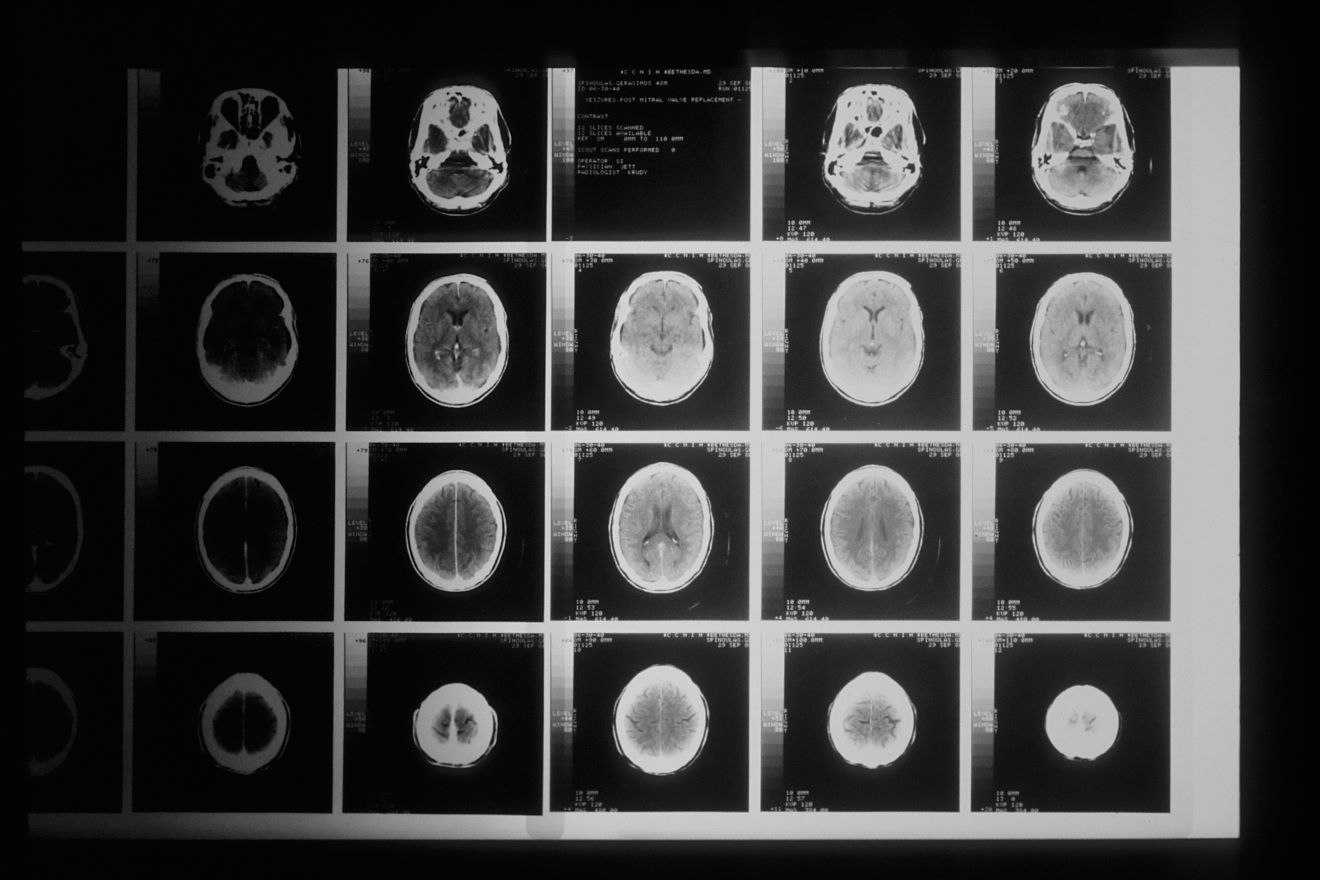

Studiju su vodili istraživači iz Istraživačkog centra Jülich i RWTH Sveučilišta u Aachenu u Njemačkoj, a uspoređivala je snimke mozga muškaraca kojima je dijagnosticirana psihopatija s onima zdravih dobrovoljaca bez te dijagnoze.

Znanstvenici su zaključili da razlike u strukturi mozga ne utječu na emocionalne osobine, ali da je kod osoba s psihopatijom smanjeno područje mosta u moždanom deblu, talamus, bazalne ganglije i insularni korteks, što utječe na impulzivno i antisocijalno ponašanje.

Štoviše, mozgovi ispitanih psihopata bili su u prosjeku oko 1,45 posto manji u odnosu na mozgove osoba iz kontrolne skupine. To je teško jednoznačno protumačiti, no moglo bi ukazivati na probleme u razvoju kod osoba koje se klasificiraju kao psihopati.